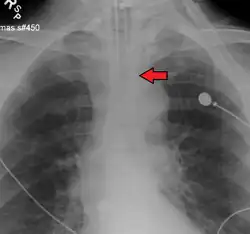

Ideally, at least one of the methods utilized for confirming tracheal tube placement will be a measuring instrument. Waveform capnography has emerged as the gold standard for the confirmation of tube placement within the trachea. Other methods relying on instruments include the use of a colorimetric end-tidal carbon dioxide detector, a self-inflating esophageal bulb, or an esophageal detection device.[35] The distal tip of a properly positioned tracheal tube will be located in the mid-trachea, roughly 2 cm (1 in) above the bifurcation of the carina; this can be confirmed by chest x-ray. If it is inserted too far into the trachea (beyond the carina), the tip of the tracheal tube is likely to be within the right main bronchus—a situation often referred to as a "right mainstem intubation". In this situation, the left lung may be unable to participate in ventilation, which can lead to decreased oxygen content due to ventilation/perfusion mismatch.[36]